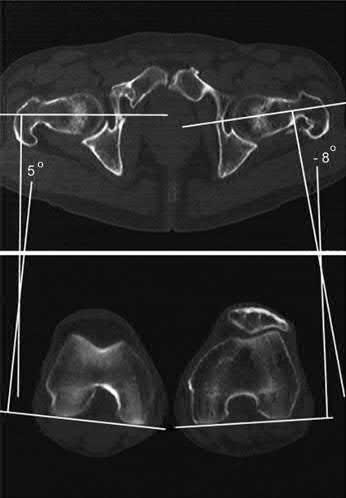

Question 1:

A 12-year-old obese boy presents with vague left thigh and knee pain. He is diagnosed with a Slipped Capital Femoral Epiphysis (SCFE) as seen in similar clinical scenarios. During percutaneous in-situ fixation, unrecognized penetration of the guide wire into the hip joint occurs. What is the most likely specific complication resulting from this technical error?

Correct Answer: Chondrolysis

Explanation:

Chondrolysis is a severe complication of SCFE characterized by rapid destruction of the articular cartilage. While it can occur idiopathically, its most established iatrogenic cause is unrecognized intra-articular hardware penetration. The 'approach-withdraw' fluoroscopic technique is required during pinning to assure pins are entirely intraosseous. Avascular necrosis (AVN) is usually due to damage to the epiphyseal blood supply (retinacular vessels) secondary to the initial displacement, forceful closed reduction, or posterosuperior pin placement.